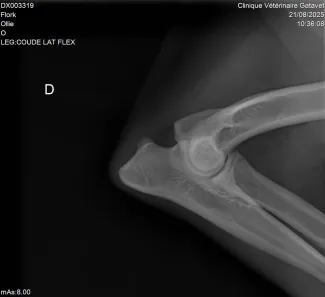

Radiographie Ollie suivi arthrose antérieur droit Gatavet 09/2025

Un examen vétérinaire avec radiographie permettra de confirmer ou non le diagnostic.